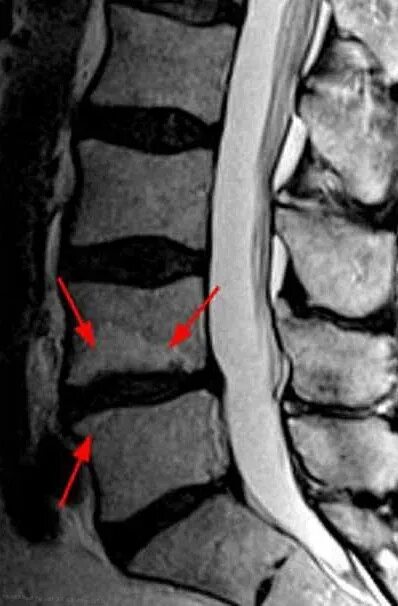

Мрт шейно поясничного отдела